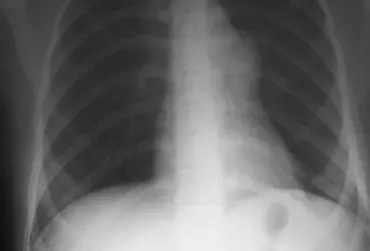

W artykule przedstawiono opis przypadku klinicznego pacjentki z przewlekłą obturacyjną chorobą płuc, której przyczyną jest rozstrzenie oskrzeli. Wybór zabiegów do terapii oddechowej uzależniony był przede wszystkim od rodzaju choroby i stopnia jej zaawansowania.